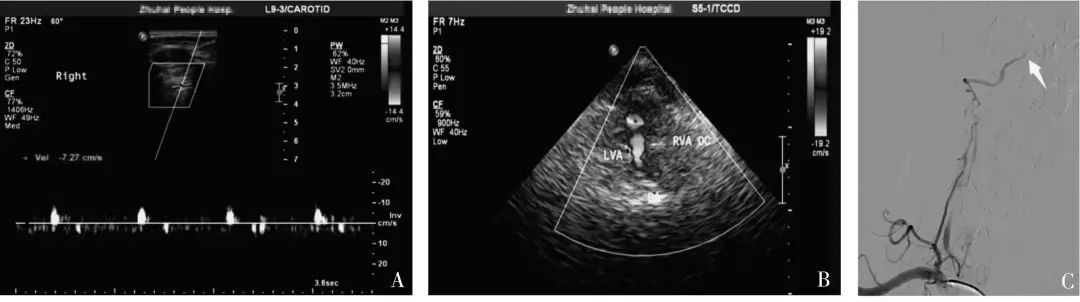

2019年9月,暨南大學(xué)附屬珠海醫(yī)院報(bào)道了一項(xiàng)研究[1],經(jīng)由CTA或DSA結(jié)果證實(shí)為單側(cè)椎動(dòng)脈顱內(nèi)段閉塞患者40 例,由未規(guī)范培訓(xùn)組醫(yī)師和規(guī)范培訓(xùn)組醫(yī)師分別進(jìn)行血管超聲檢查,將兩組超聲診斷結(jié)果與金標(biāo)準(zhǔn)結(jié)果進(jìn)行比較,并對(duì)兩組不同資歷醫(yī)師進(jìn)行診斷一致性分析。

結(jié)果:規(guī)范培訓(xùn)組診斷椎動(dòng)脈顱內(nèi)段閉塞的敏感度及符合率(均為95%)明顯高于未規(guī)范培訓(xùn)組(均為75%),不同資歷的超聲醫(yī)師對(duì)于椎動(dòng)脈顱內(nèi)段閉塞的一致性檢驗(yàn)結(jié)果Kappa 值為0.273,診斷一致性較差。

中國(guó)腦卒中血管超聲檢查指導(dǎo)規(guī)范[2]指出:若椎動(dòng)脈閉塞于小腦后下動(dòng)脈分支之前,椎動(dòng)脈顱外段可探及低速單峰型(無(wú)舒張期血流信號(hào));若椎動(dòng)脈閉塞于小腦后下動(dòng)脈之后,椎動(dòng)脈顱外段可探及低速高阻型(舒張期流速低平)血流信號(hào)。

本研究中,未規(guī)范培訓(xùn)組椎動(dòng)脈椎間隙段頻譜形態(tài)呈“高阻型”10 例中,全部診斷為椎動(dòng)脈發(fā)育不良,“單峰型”30 例全部診斷為顱內(nèi)段閉塞。

當(dāng)椎動(dòng)脈椎間隙段內(nèi)徑≤2.5 mm,頻譜形態(tài)呈低速高阻型改變時(shí),既有可能是椎動(dòng)脈發(fā)育不良,也有可能是椎動(dòng)脈顱內(nèi)段閉塞,此時(shí)應(yīng)聯(lián)合TCCS(或TCD) 檢查,直觀地從枕窗觀察雙側(cè)椎動(dòng)脈顱內(nèi)段的血流充盈情況。